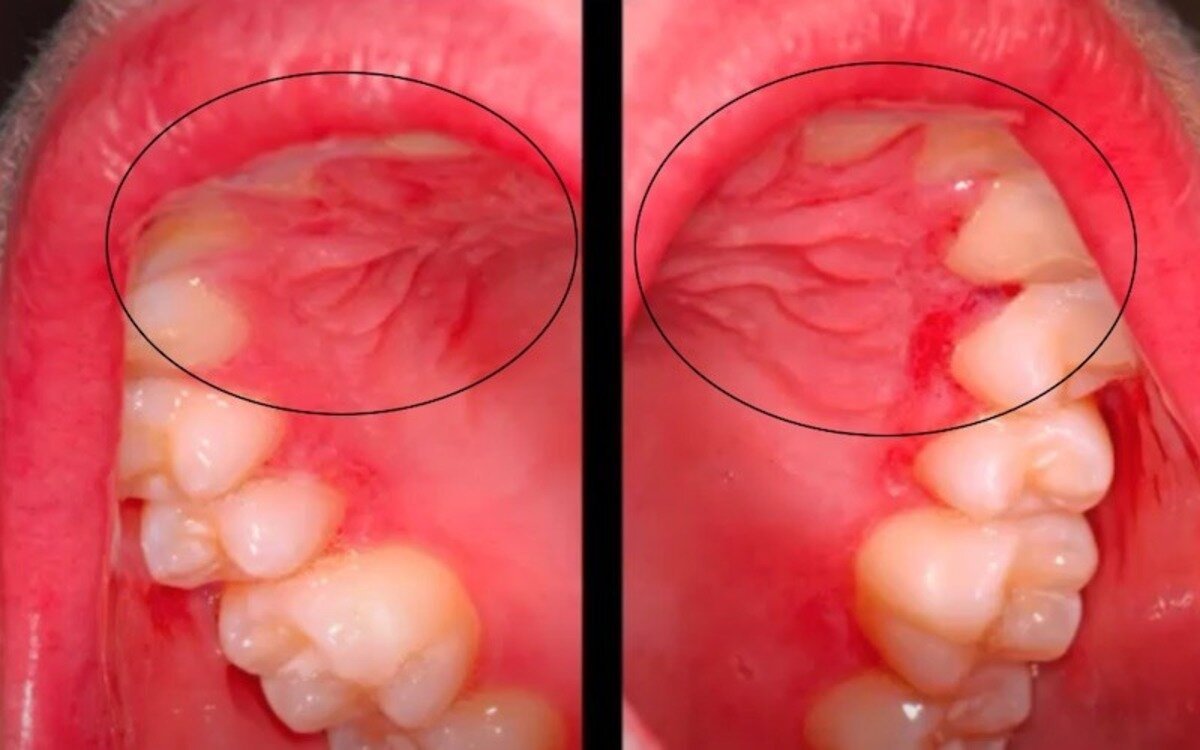

Болезнь Крона во рту проявляется язвенными поражениями, которые вызывают дискомфорт и боль при глотании. На коже при заболевании могут возникать высыпания и эрозии, которые локализуются в области живота и нижних конечностей. У людей с болезнью Крона также могут воспаляться слизистая (конъюнктивит) и радужная (ирит) оболочки глаза. Как выглядит болезнь Крона, можно увидеть на фото.

Внекишечные проявления болезни Крона могут включать язвы во рту, припухшие губы, красные пятна в уголках рта. Язык при болезни Крона может быть покрыт небольшими язвами, которые вызывают боль, жжение и дискомфорт во время еды, питья, чистки зубов. При болезни Крона появляются сыпь красного цвета, припухлость и чувствительность кожи при пальпации, бугорки под кожей (особенно в области нижних конечностей).